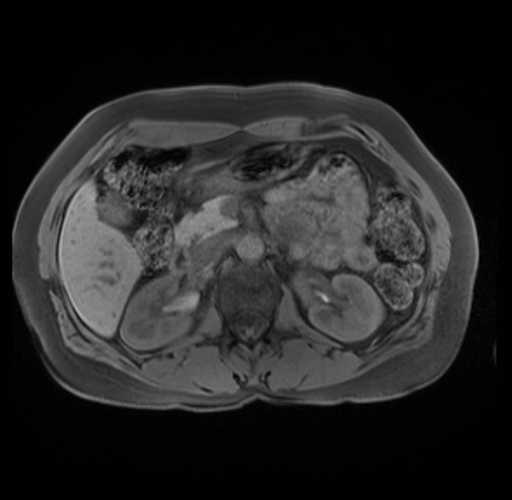

Imaging Analysis

Look through the patient's CT scan to identify any areas of concern for the necessary procedure.

Based on your CT findings, which issue(s) are present and would give reason for "planned slowing down moment(s)" in this case?

Considering a standard distal pancreatectomy procedure, what step(s) of the operation would you do differently in this case?